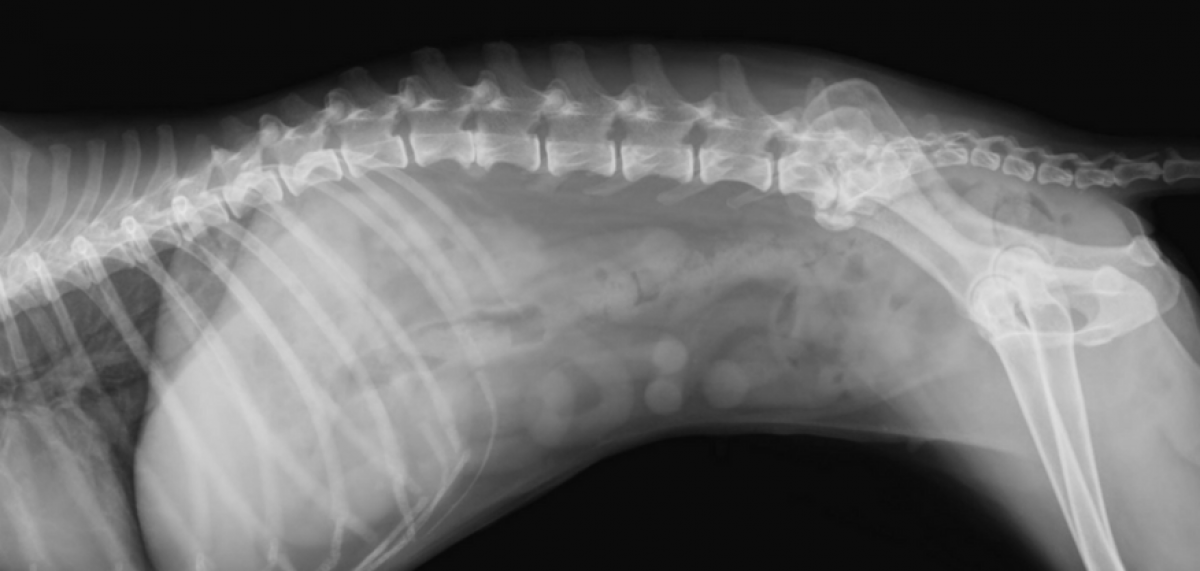

Røntgenundersøkelse av skjelett, muskulatur, bryst- og bukhule er en viktig del av den spesielle undersøkelsen og diagnostiseringen.

Kontrastundersøkelser blir gjennomført i organer og ledd for riktig behandling og sikker diagnostisering. Våre røntgenundersøkelser blir foretatt med digitalt røntgenapparat som gir en førsteklasses kvalitet på bildene og dermed en sikrere avlesning.